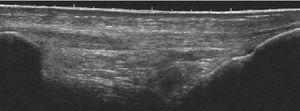

Utilizando el equipo E-A, mediante corte transverso sobre el músculo contusionado se observa (fig. 1A) la imagen de predominio hiperecoico y en su interior la zona oval hipoecoica con mala delimitación de los bordes y con mala definición del contenido, lo que la hace compatible con un lesión muscular por mecanismo extrínseco. La imagen del equipo E-B presenta también un aspecto hiperecoico, si bien la zona oval hipoecoica/anecoica presenta bordes muy bien marcados y se observa con detalle que en el interior existe un contenido heteroecoico que corresponde a las zonas de reabsorción del hematoma (fig. 1B). Todos estos signos permiten el diagnóstico preciso de la lesión muscular extrínseca.

Figura 1 A) En el corte transverso con E-A se observan imágenes hipoecoicas en el vientre del músculo gastronemio interno. B) En el mismo corte, con el equipo E-B se delimita exactamente la zona lesionada del área muscular indemne que lo rodea.